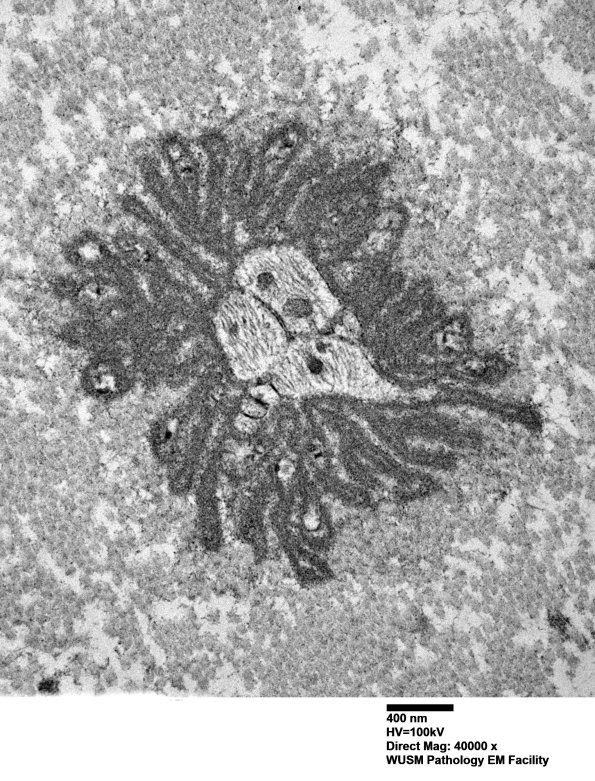

There are minimally preserved bands, a likely impediment to axonal regeneration.